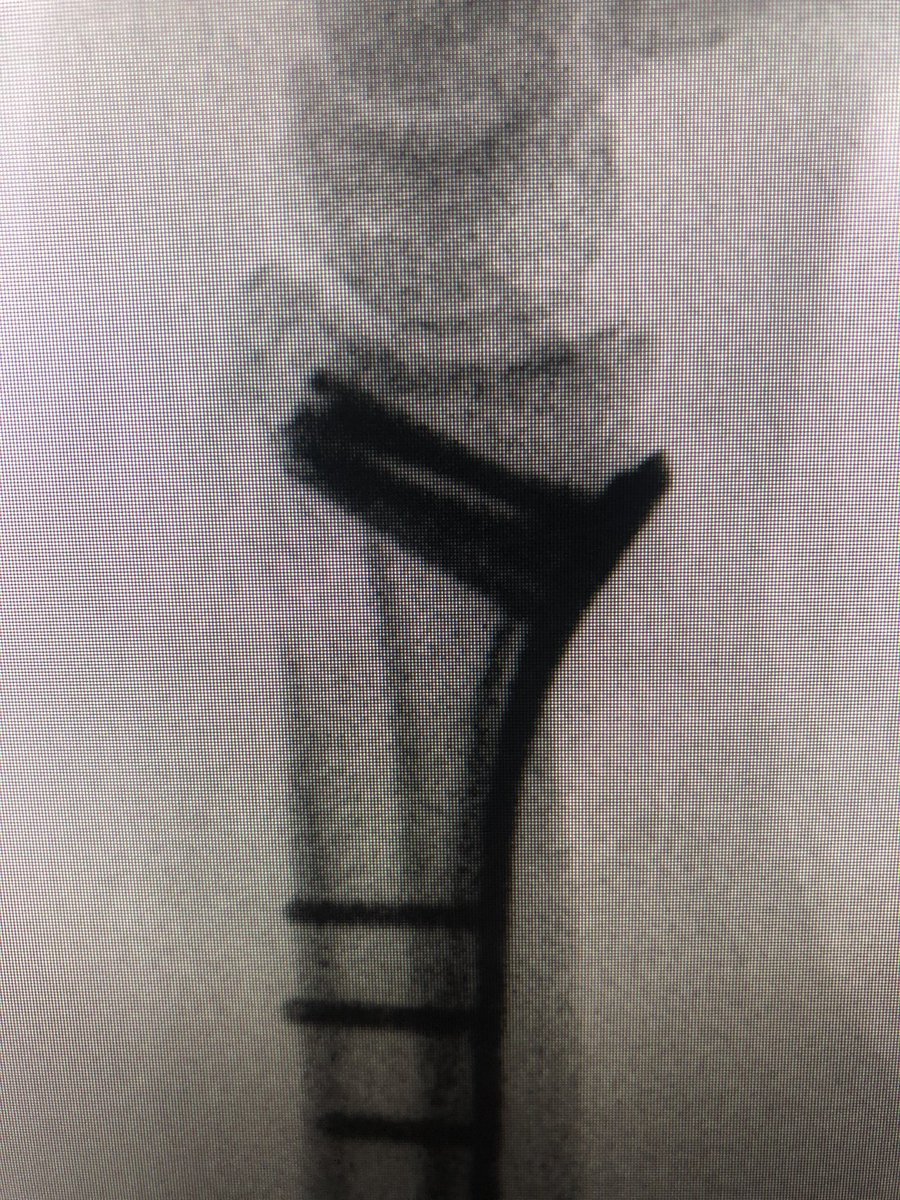

Single oblong hole non locking screw placed in the limb of the plate, allows rotation.

The lamina spreader goes in with the oblong hole cortical screw loosened a couple turns, this corrects alignment, tighten the screw and place more proximal locking screws to โ€˜fixโ€™ the plate position now. Inclination, DRUJ and plate position are corrected.